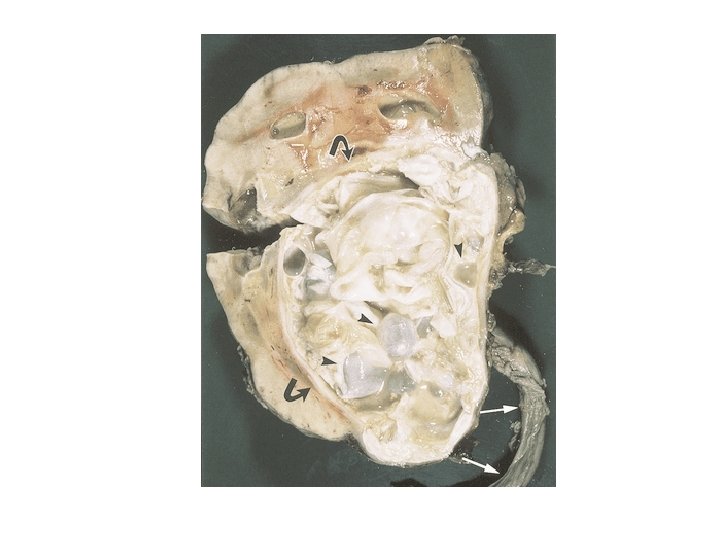

Hydatid Cyst Structure • The hydatid cyst has three layers: (a) the outer pericyst, composed of modified host cells that form a dense and fibrous protective zone; (b) the middle laminated membrane, which is acellular and allows the passage of nutrients; (c) the inner germinal layer, where the scolices (the larval stage of the parasite) and the laminated membrane are produced.

• Daughter vesicles (brood capsules) are small spheres that contain the protoscolices and are formed from rests of the germinal layer. Before becoming daughter cysts, these daughter vesicles are attached by a pedicle to the germinal layer of the mother cyst. At gross examination, the vesicles resemble a bunch of grapes.